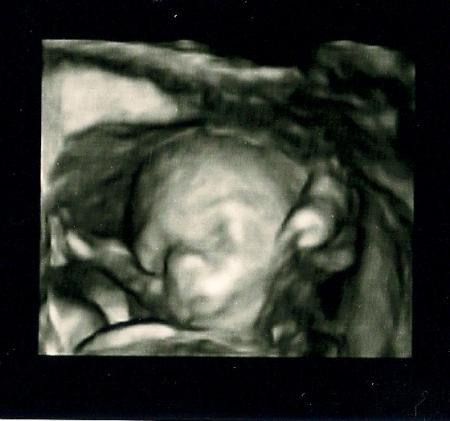

So, ich melde mich nach 4 ganz langen Tagen zurück. Ich war endlich mal wieder zu Hause und konnte nun auch endlich anfangen etwas für meinen Spatz vorzubereiten. Also ich hab zwei Schränkchen weiß gestrichen :) Aber viel wichtiger ist, dass wir seit Freitag nun endlich wissen, dass wir einen kleinen Jungen bekommen!! Und heut ist auch noch Halbzeit, also alles auf einmal ;) Schönen Abend Euch noch!! Nine und ihr kleiner Boxer

Bild zu Viel passiert am Wochenende :) + Bilder - Forum für September - Mamis